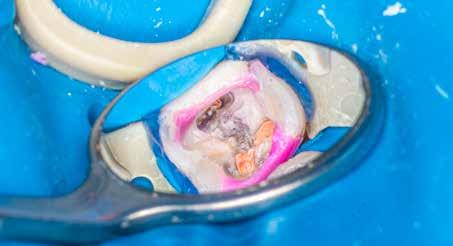

A terület érzéstelenítése és a kofferdám felhelyezését követően az ideiglenes tömést eltávolítottuk, majd a fogbélkamrát 5,25%-os NaOCl-oldattal feltöltöttük, amelyet ultrahang segítségével aktiváltunk (4–5. ábra). A fogbélkamrában lévő visszamaradt szuvasság eltávolítását követően a területet vízzel lemostuk, majd az egész területet puszterrel leszárítottuk. A terület előkészítését követően az izolálást

4. ábra: A kofferdám felhelyezése után látható állapot. Az ideiglenes tömés még nem került eltávolításra.

5. ábra: Az ideiglenes tömés eltávolítását követően látható állapot.

6. ábra: A visszamaradt szuvas foganyag eltávolítását és a folyékony kofferdám felhelyezését követően kialakult helyzet.

folyékony kofferdám felvitelével tökéletesítettük, majd polimerizáltuk. Ezt követően a lézeres kezelés előkészítése részeként a hozzáférési nyílás méretét megnöveltük (6. ábra). A lézeres aktivációhoz egy SkyPulse lézerkészüléket (Fotona) használtunk AutoSWEEPS üzemmódban. Egy lapos végű 300/20 SWEEPS hegyet 1 W teljesítmény mellett alkalmaztunk (7. ábra). A fogbélkamrát NaOCl-oldattal feltöltöttük, majd a vezetőszál hegyét enyhén a mesiobuccalis csatorna